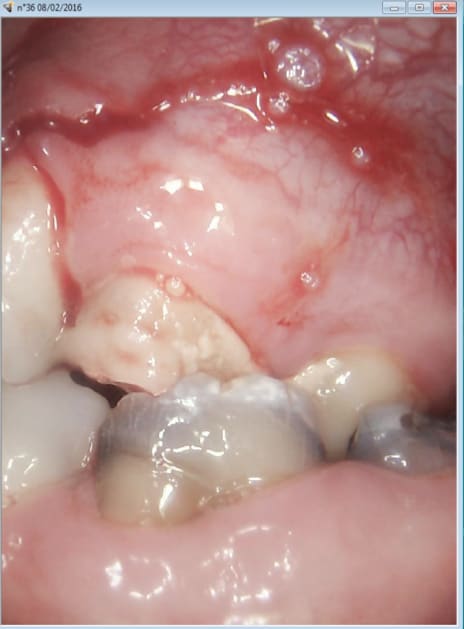

Miracle la 26 était vivante. -))))

Pas facile de trouver les 4 canaux c'est le Mv1 qui a été le plus dur une fois n'est pas coutume ! -)))

Le reste va dégager chez le stomato. J'ai viré la 24 en en chiant assez comme ca après l'endo de 26. Chacun doit faire sa B.A. -)))

J'ai juste la place de faire une ceram sur 26 une fois que 36 sera enlevée. -))))

Ah ouai j'avais pas bien regardé les photos. Comment as-tu trouvé MV1, parce que sur la photo en haut à droite on ne le voit pas du tout.

Le feeling et un bon sx protaper. -)))

Et pour les photos c'est un microscope ou c'est une caméra endobuccale?

C'est vrai ma reconstitution préendo était bien collée à l'entrée du MV1 dommage que le patient consultait à cause de douleurs. Il serait venu 15 jours avant ca aurait pu le faire. -)

Ha non à ce degré de saleté et de négligence on est hors indication d'un onlay pour moi.

On est pile-poil dans l'indication d'une CCM avec un sertissage périphérique légèrement sous-gingival.